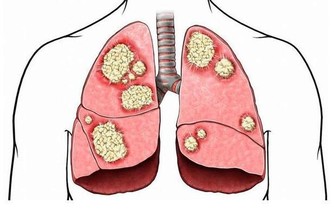

肺部是呼吸系統重要的器官,人們的輕鬆的呼吸、乾淨的血液都依靠肺部的運行。當肺部出現了健康問題,對於整個身體健康是有很大影響的,甚至會危及到生命,所以及時知曉肺部的求救信號是非常重要的。睡覺時有哪些異常情況是肺在求救呢?接下來讓我們一起來了解一下。

睡覺的時候哪些異常情況是肺在求救呢?

1、劇烈的咳嗽

肺部出現健康問題,一個最為重要的症狀就是它會出現劇烈的咳嗽,在夜間甚至會達到影響人睡眠的地步。如果是平常感冒引發的咳嗽,通過及時有效的治療,在幾天之內就能夠好轉,哪怕不去治療也會在兩週之內痊癒。

但是如果咳嗽非常的嚴重,長時間的也無法好轉,尤其是在夜間咳嗽,甚至會影響人的睡眠,這就有可能是肺部出現健康問題的症狀,最有可能是肺炎引起的,如果得不到及時的治療和控制,引發胃癌也是有可能的事。這種情況在吸煙的人身上非常的常見,如果平常愛吸煙,晚上劇烈的咳嗽,一定要去醫院檢查一下肺部,看是否健康。

2、半夜醒來

肺部有疾病的人在半夜經常會醒來,大約會在三到五點之間。之所以會在這個時間醒來,是因為這個時間段是身體的肺部的排毒時間,肺部的功能出現了障礙,人們就會在這個時間段醒來,肺部積累了過多的毒素,疾病也會找上門來。如果經常在這個時間段醒來,千萬不要認為是睡眠出現了問題,單純的去加一些幫助睡眠的措施是沒有辦法解決根本問題的,該醒來的時候還是會醒來。這時候就要仔細的考慮,如果還伴隨著咳嗽等症狀還是應該往肺的方向考慮,檢查一下才能放心。

3、呼吸困難

肺部有疾病的人,首先影響的就是人的呼吸,呼吸對人的重要性恐怕不必再說,呼吸停止了,生命也會走向終結。肺部是呼吸系統重要的器官,肺出現問題,呼吸也會產生異常。當在晚上睡覺的時候,經常的胸悶氣短,甚至呼吸困難,讓人在睡夢中突然醒來,大喘幾口氣才會好轉,就非常有可能是肺部受損嚴重的表現。出現這種情況很有可能是睡眠呼吸暫停綜合症,為了弄清楚原因,還是去醫院檢查一下比較好。

肺部受損是一件比較重大的事,出現了肺部疾病也不要拖延,一定要及早治療,這樣才能把後果盡量的降到最低。